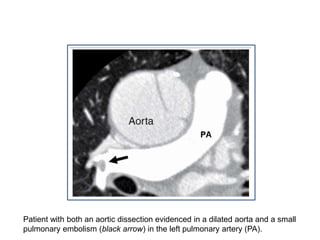

Patient with both an aortic dissection evidenced in a dilated aorta and a small

pulmonary embolism (black arrow) in the left pulmonary artery (PA).

PULMONARY EMBOLISM • MDCTcan diagnose acute and chronic pulmonary thromboembolism. • It has replaced nuclear ventilation/perfusion scans as the primary imaging study in the diagnosis of acute pulmonary embolism. • The cross-sectional view of the main and proximal right and left pulmonary arteries provides clear delineation of the proximal extent of the thrombi, which is essential for successful surgical treatment. • Accuracy for the diagnosis of pulmonary embolism using multidetector CT is high, with a negative predictive value of 99% among patients with low to moderate pretest likelihood, although accuracy for the detection of subsegmental pulmonary emboli may be limited. Quiroz R, Kucher N, Zou KH, et al: Clinical validity of a negative computed tomography scan in patients with suspected pulmonary embolism: A systematic review. JAMA 293:2012, 2005.